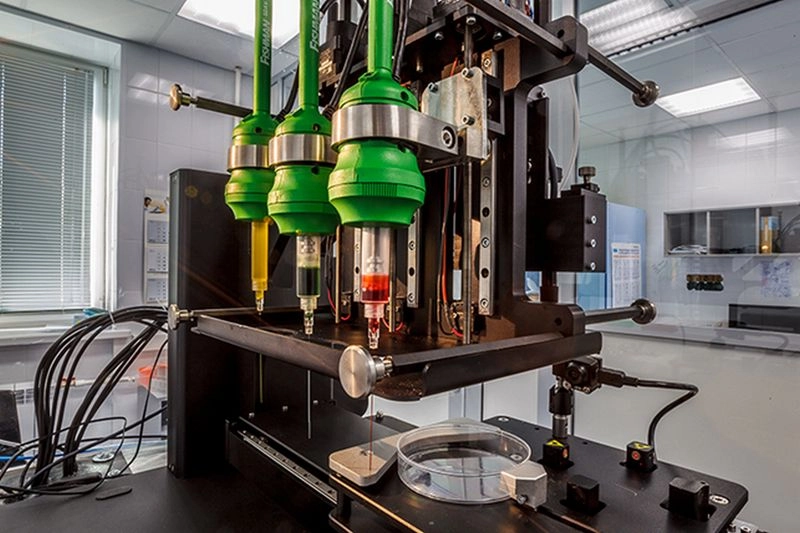

Специалист работает с российским биопринтером FABION 2 в лаборатории / © 3D Bioprinting Solutions Социальная реклама. ЧУ «Центр коммуникаций», ИНН 9705152344, erid 2VtzqvZpfv9.

Высокоточный 3D-биопринтер для создания живых тканей и органов / © Научный дивизион «Росатома»

До середины 2010-х биофабрикацию пытались вести на основе отдельных клеток, распыляемых гидрогелем. Плотность клеток в гидрогеле была низка, поэтому выращивание из нее тканей шло медленнее. В 2014 году российская компания 3D Bioprinting Solutions создала экструзионный биопринтер Fabion. Он впервые распылял предварительно выращенные сфероиды, что резко ускорило процесс получения целевой ткани.

Научно-образовательная лаборатория тканевой инженерии и регенеративной медицины НИТУ МИСИС, компактный биопринтер FABION / © МИСИС

Биопринтер в российской лаборатории / © 3D Bioprinting Solutions